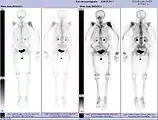

- Projection d'intensité maximale avec divers traceurs

- Projection d'intensité maximale d'un TEP/scanner avec de la choline. On reconnaît clairement l'enrichissement physiologique dans le foie, le pancréas, les reins, la vessie, larate, la moelle osseuse et les glandes salivaires. La métastase osseuse se trouve dans le pubis à gauche.

- TEP/scanner d'intensité maximale avec du fluorodésoxyglucose (18F) (FDG) avec un cancer du sein en métastases. Tumeur primaire dans le sein droit. Métastases dans les ganglions lymphatiques du médiastin et dans les poumons. Les métastases osseuses sont mieux délimitées dans la vue avec 18F-NaF (vidéo suivante).

- TEP/scanner au maximum d'intensité avec du 18F-NaF (fluorure de sodium) sur un cancer du sein en métastases dans le crâne, la colonne vertébrale, le bassin, les côtes, la clavicule gauche et le fémur droit. Même patiente que dans la vidéo précédente (FDG).

Les métastases osseuses de divers cancers peuvent être très bien visualisées par TEP/scanner. Le procédé est plus sensible que la TEMP et notablement plus que la scintigraphie, cependant, plus sophistiquée, et donc plus onéreuse. Selon de type de tumeur primitive, on utilise divers traceurs, mais le plus souvent le Fluorodésoxyglucose (18F) et le fluorure de sodium NaF (18F), et aussi pour le cancer de la prostate la choline (18F). L'activité métabolique de la tumeur est le plus souvent bien visible avec le FDG, et la réaction de l'os à la métastase avec le NaF[124].